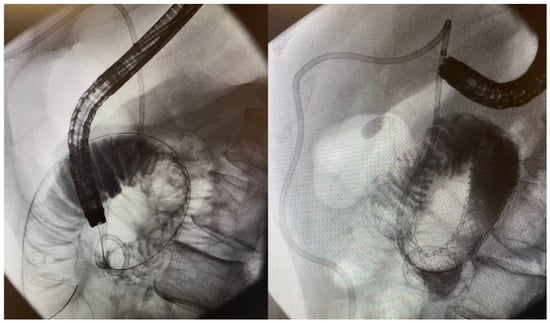

5.4. Endoscopic Gastroenterostomy

6.2. Gastroduodenal